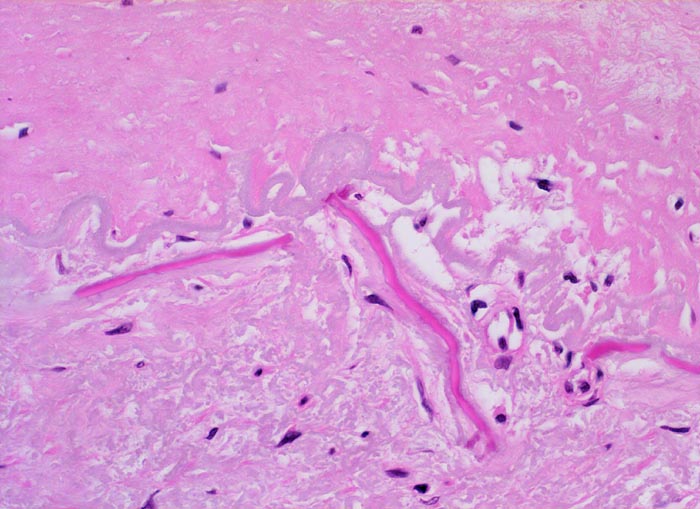

Die Atherosklerose befällt Arterien vom elastischen Typ und die grossen und mittelgrossen Arterien vom muskulären Typ. Die früheste Läsion, der Lipidstreifen, besteht aus einer fokalen Akkumulation von Lymphozyten und glatten Muskelzellen und von Serumlipoprotein in Makrophagen der Intima (> 5267). Zirkulierende Monozyten infiltrieren die Intima, nehmen alteriertes LDL Cholesterin auf und wandeln sich dadurch in Schaumzellen um. Diese Läsion kann sich durch zunehmende Lipidakkumulation und Migration sowie Proliferation von Myofibroblasten zum Präatherom mit wenig extrazellulären Lipidablagerungen und schliesslich zum Atherom (> 9003) mit zentral konfluierten extrazellulären Lipidmassen (> 9004) und nekrotischem Detritus weiterentwickeln. Die eingewanderten Mediamyozyten produzieren extrazelluläre Matrix, welche über dem Atheromkern aus extrazellulärem Lipid, Schaumzellen, Kalziumsalzen und Zellschutt eine fibröse Deckplatte bildet. Die atheromatöse Plaque kann narbig umgebaut werden, dystroph verkalken und konsolidieren oder zu einer komplizierten Plaque fortschreiten. Komplizierte Läsionen sind charakterisiert durch Ulzeration, Thrombose oder Plaqueeinblutungen. Bei einer Verletzung des Endothels oder einer Ruptur der fibrösen Deckplatte kommt der thrombogene Inhalt des Lipidkerns in Kontakt mit dem zirkulierenden Blut und es bildet sich eine Gefässthrombose. Wiederholte Rupturen mit nachfolgender Organisation der Thrombose vergrössern die Plaque und führen zu einer zunehmenden Gefässeinengung. Bei langsam gewachsenen schweren Stenosen bildet sich oftmals ein guter Kollateralkreislauf aus, welcher bei plötzlichem Gefässverschluss einen Infarkt im Versorgungsgebiet der verschlossenen Arterie verhindern kann. Grosse inter- und intraindividuelle Unterschiede bezüglich der relativen Anteile von weichen atheromatösen und derben fibrotischen bzw. verkalkten (> 4557) Bestandteilen der Plaques bestimmen wesentlich die Stabilität bzw. Vulnerabilität der Läsionen. Der Lipidanteil liegt bei rupturierten Plaques generell höher als bei Plaques mit intakter fibröser Deckplatte.

• Intimafibrose mit fokalen grobscholligen(dystrophen) Verkalkungen und Einblutungen in der unteren Hälfte des Arterienquerschnitts.

• Fibröse bindegewebige Deckplatte über dem Atheromkern

• Atherome in der Intima mit zentraler Nekrose, Cholesterinkristallen, Entzündungszellen und gelben Hämosiderinablagerungen oder Einblutungen.

• Partielle Zerstörung der Lamina elastica interna.

• Atrophie der glatten Muskulatur der Media.